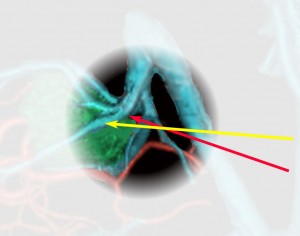

松果体腫瘍へのOTAのルートです。occipital transtentorial apporachというのは黄色の矢印に沿ってガレン大静脈の下に入る方法であり,そこから松果体部を通って第3脳室内へ直線的な視野が展開します。

一方,赤の矢印に沿ったルートは parieto-occipital transtentorial approachです。このルートでは内大脳静脈 internal cerebral veins を見ることがかなり難しいです。更に,第3脳室に入るためには脳梁膨大部 spleniumを切断する必用があります。ただし,小脳上部や第4脳室を見るときにはparietal寄りのルートを使います。

この図は左後頭開頭で後頭葉を牽引して見える時の,galenic systemの各静脈の位置関係を示します。太さもこのくらいのものです。解りやすいように,少々parietal sideからみています。

ガレン大静脈に流入する内大脳静脈 ICVとローゼンタール静脈とprecetral cerebellar veinの位置関係を俯瞰した図です。この例ではガレン大静脈と直静脈洞の接合部が高い位置にあります,galenic pointが高い,あるい接合部がsteep angleであると表現します。個人差が大きいものですが,galenic pointが高い方がガレンの可動性が大きくて手術はしやすいといえます。

実際に見る静脈はこの領域です。図の説明は側方から見ていますが,手術では腹臥位で後頭極方向からみます。ですから,黄色の矢印の視軸でローゼンタール静脈を見るので,ローゼンタール静脈は術野の深いところに沈んで行くように見えます。同様に赤の矢印でICVを見ますから,ICVも深く沈んで行くように走行して行くように見えます。従って,両静脈を剥離して行くと手術操作野は深く深くなります。